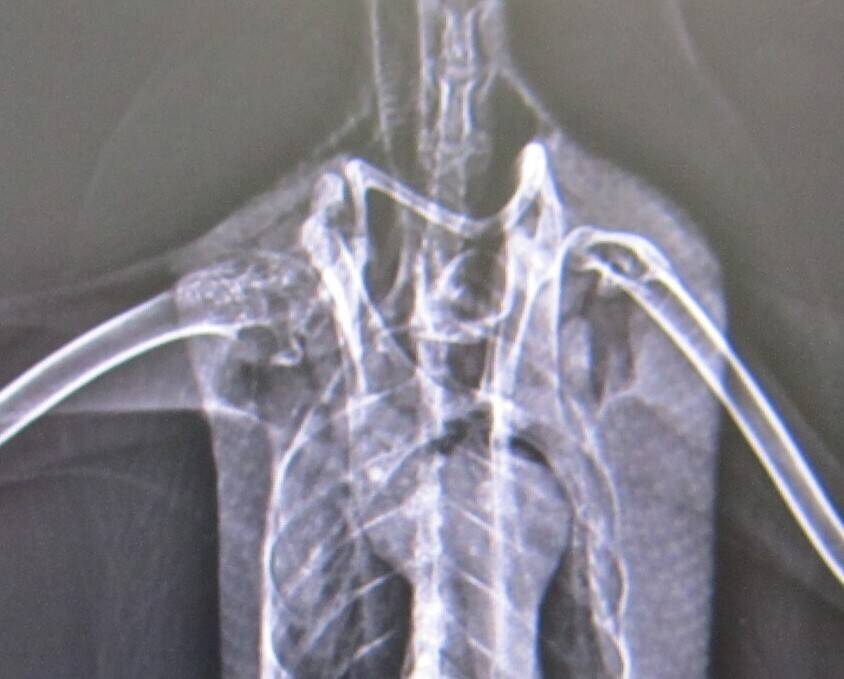

患部をアップにしてよ~く見てみると・・・

左右にズレがあるのがわかりますね。ここが患部です。